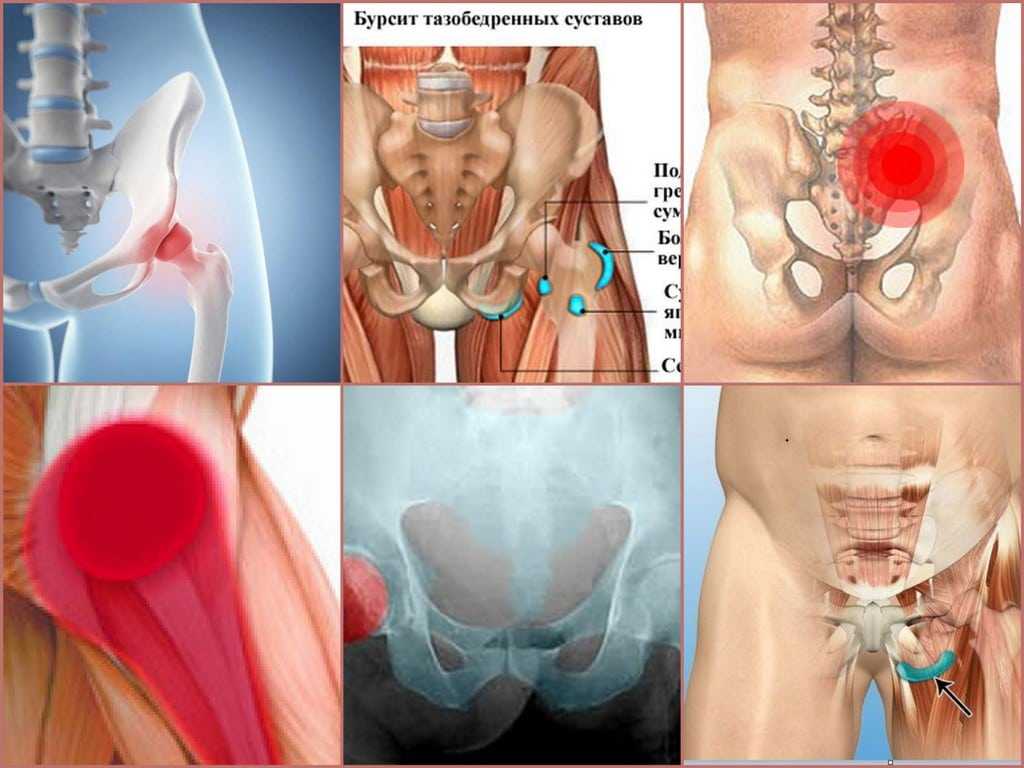

Здоровье суставов: Трохантерит и его влияние на мышцы